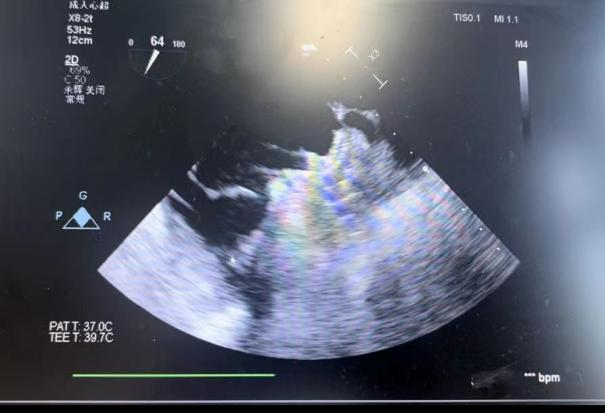

潘教授通过食路超声从4个分歧的角度来观察患者左心耳的状态情况,显示心耳为反鸡翅型,地位较低,锚定区为23mm,封堵区为26mm。术者结合多年的临床经验,最终选用型号为LT-LAA-2632的LAmbre?左心耳封堵器对患者进行封堵。

▲(图:通过超声观察进行穿刺)

在食路超声疏导下进行房距离穿刺,由于心耳为反鸡翅型,穿刺位点需靠下靠前,潘教授先在90度双腔切面将定位靠下,再在45度自动脉短轴切面将定位靠前。穿刺成功后上导丝互换俄罗斯贵宾会集团LAnavi?分段控弯导引系统送诚意耳口部,经过A、B双弯的调整使得鞘管轴向与心耳同轴,获得梦想封堵地位。而后推送钢缆开释出固定盘,锚定后退鞘开释出封堵盘。超声下观察贴合优良,无显著残存分流,牵拉测试不变,即开释左心耳封堵器。开释后再次通过超声各个角度进行验证,封堵了局美满有效,整个过程趁热打铁,手术获得了极大的成功。

牵拉测试不变 美满有效封堵